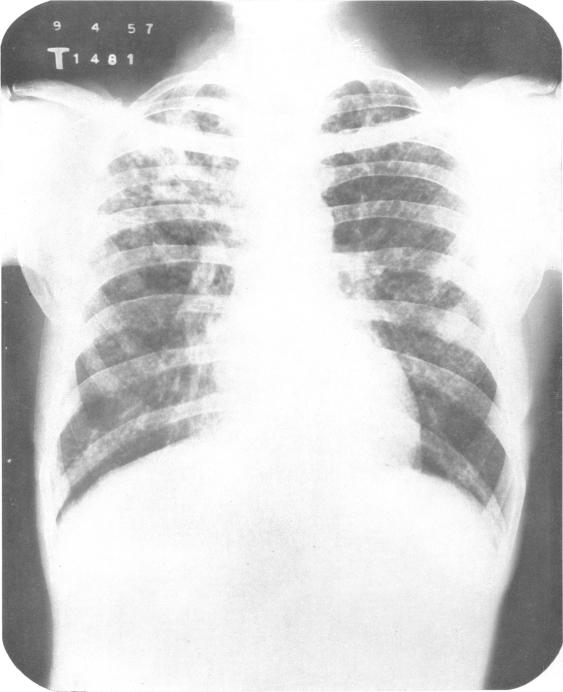

In India, as in most under-development countries, the tuberculosis problem is aggravated by an acute shortage of sanatorium beds. The number of active cases of tuberculosis in the country has been estimated at 2 (1/2) million, but only 23 000 tuberculosis beds are available. In these circumstances great importance attaches to the possibility of applying mass domiciliary chemotherapy as a substitute for sanatorium treatment in cases of pulmonary tuberculosis. The findings of the present study, based on a comparison of the two types of treatment over a period of 12 months, show that despite the manifest advantages of sanatorium care-rest, adequate diet, nursing and supervised medicine-taking-the merits of domiciliary chemotherapy are comparable to those of sanatorium treatment, and that it would therefore be appropriate to treat the majority of patients at home, provided an adequate service were established.